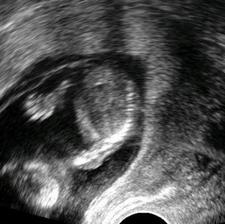

Testy + utz + bříško ♥